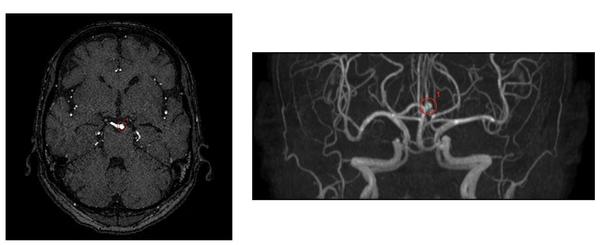

【検出事例】

・旧モデルと比較して「偽陽性」が低減した症例

・脳底動脈の検出事例

※いずれの検出例もイメージであり,実際の製品表示とは異なる場合がある。